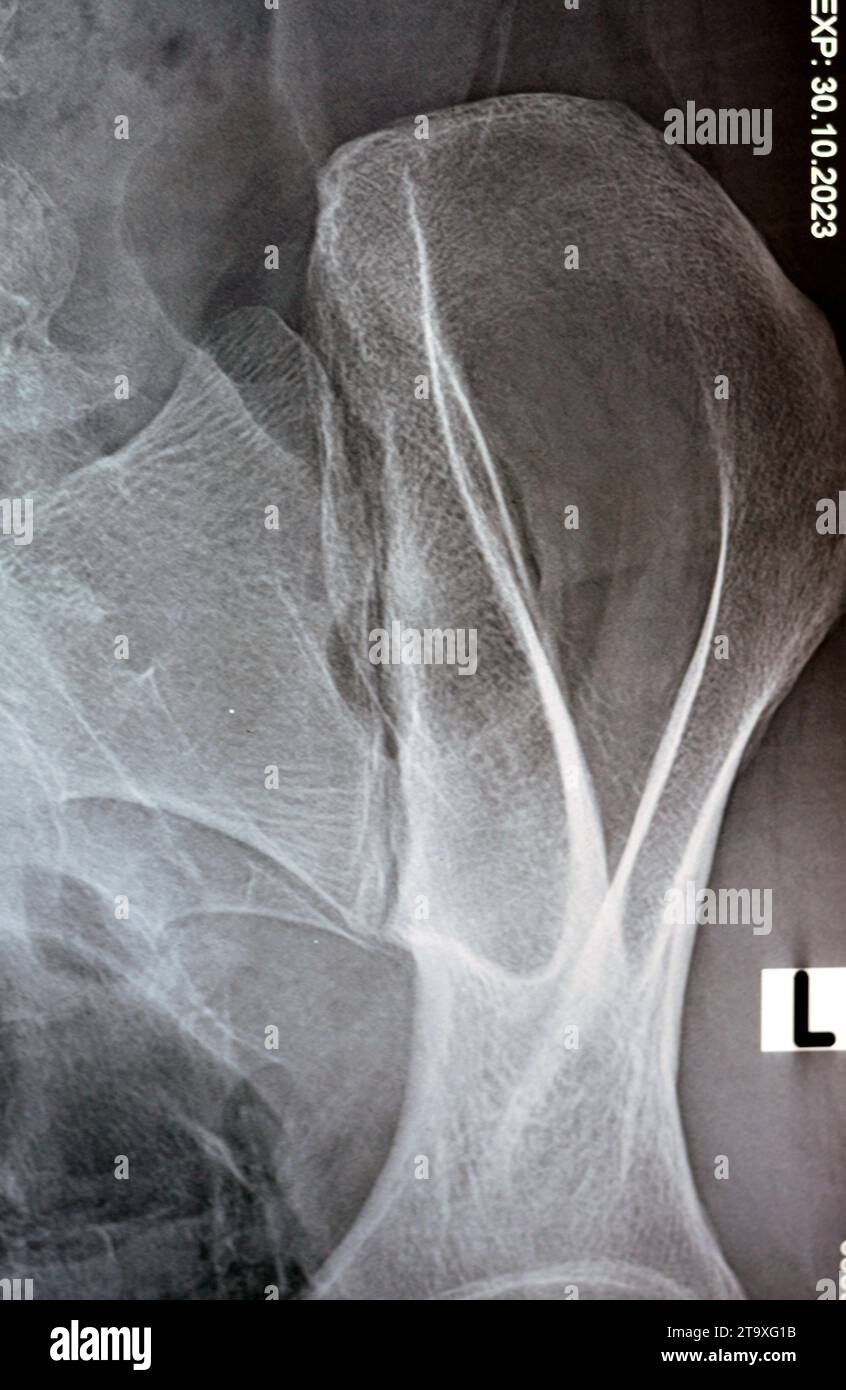

Radio Sacro Iliaque Normale . Bassin PinkyBone relations: piriformis muscle, lumbosacral trunk; internal, external and common iliac veins Case study, Radiopaedia.org (Accessed on 22 Mar 2025) https://doi.org/10.53347/rID-43339

Normal Sacroiliac Joint X Ray . - Schéma de l'orientation des articulations sacro-iliaques et matérialisation du rayon incident Case study, Radiopaedia.org (Accessed on 22 Mar 2025) https://doi.org/10.53347/rID-43339